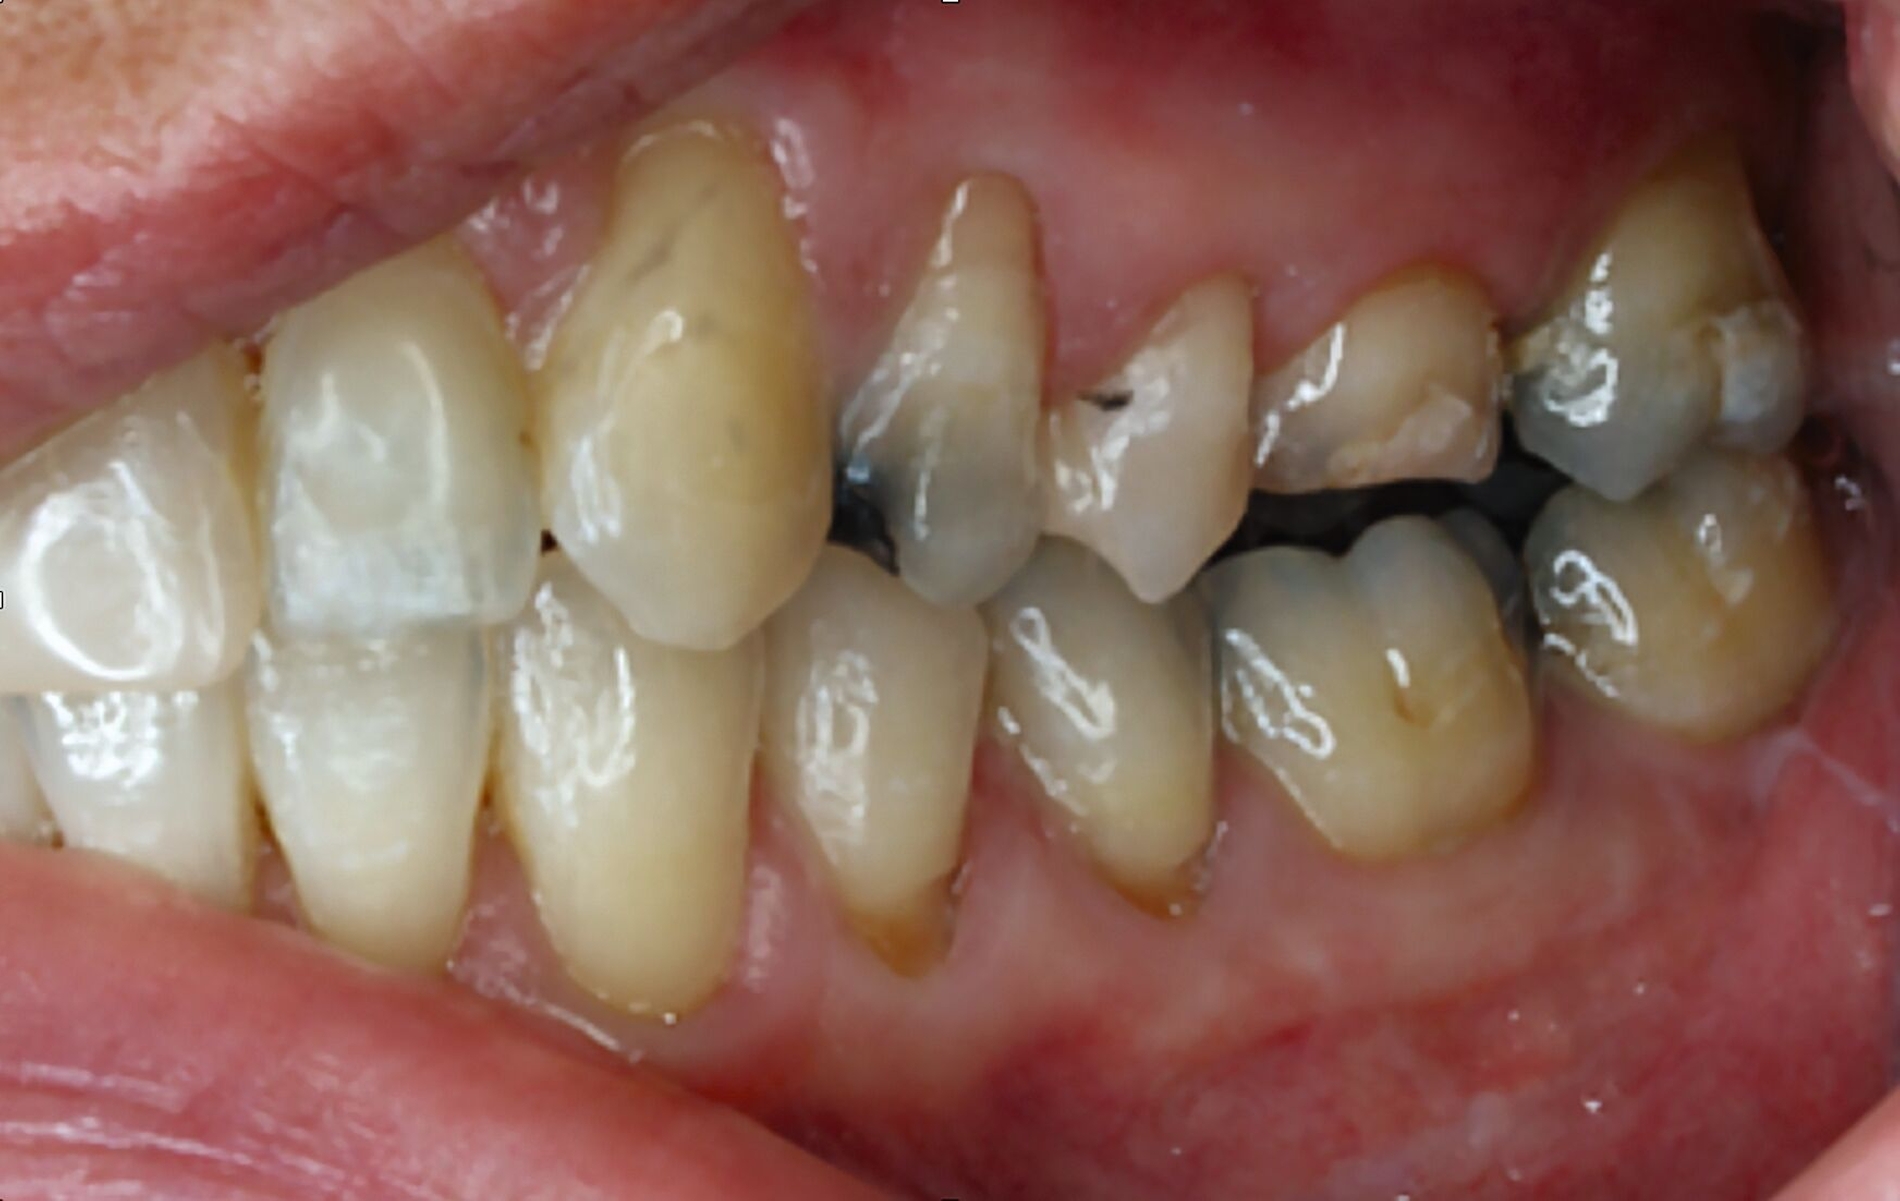

Tabelle 1 zeigt das entsprechende Befundschema mit den Taschentiefen mesial und distal, den Lockerungsgraden und den Sensibilitätsüberprüfungen mittels Kältespray (ViPr). Die Ruheschwebelage wurde mithilfe des Zielinsky-Zirkels auf 2 mm bestimmt. Die Nonokklusion im Seitenzahnbereich konnte auf circa 1,5 mm bemessen werden. Tabelle 2 spiegelt das entsprechende Okklusionsprotokoll wider. Das Okklusionsprofil wird auch in den Abbildungen 3a bis 3c deutlich.

Im Rahmen der Konsultation der Mund-, Kiefer- und Gesichtschirurgie und der Kieferorthopädie erfolgte eine erneute radiologische Bildgebung (Abbildung 4). Die Patientin wurde im Anschluss beraten, dass eine Re-Osteotomie des ehemals frakturierten und nun in Fehlstellung verheilten Collumsegments links ihr Okklusionsproblem adäquat lösen könnte. Ebenso sei eine orthognathe Umstellungsosteotomie möglich. Nach ausführlicher Aufklärung entschied sich die Patientin allerdings gegen eine chirurgisch-kieferorthopädische und für eine rein prothetische Lösung. Die Patientin hatte derart Angst vor einem erneuten chirurgischen Eingriff, dass sie selbst die Aussicht auf eine längere und invasivere prothetische Behandlungsphase nicht abschreckte.